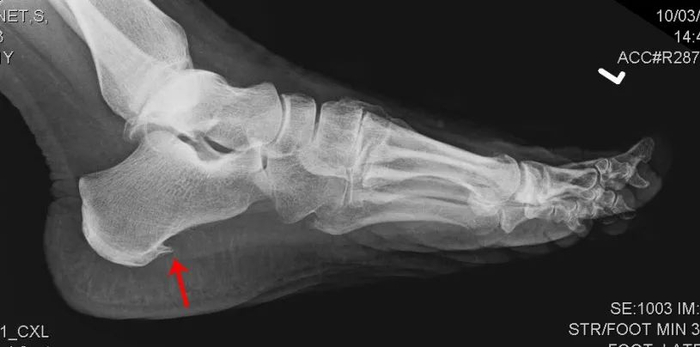

有跑友到医院检查,拍片后显示有跟骨骨刺(专业术语称为跟骨骨赘),大惊失色,会认为足底长出骨刺自然戳着疼。

其实,骨刺不是导致疼痛的主要原因,骨刺刺激了足底筋膜才是产生疼痛的主要原因,足底筋膜炎治好了,自然疼痛也就消失了,所以对于跟骨骨刺不必过度担心。